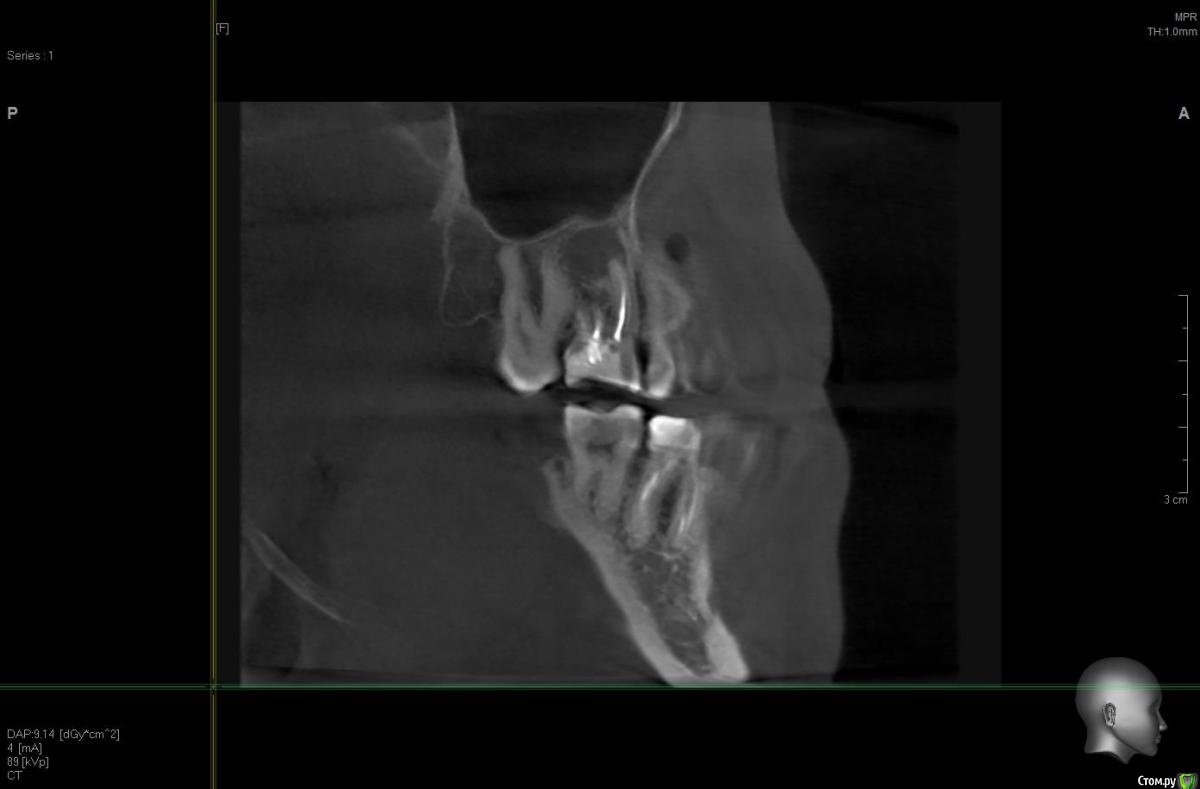

solitary Опубликовано 10 апреля, 2017 Поделиться Опубликовано 10 апреля, 2017 Доброго времени суток! Мое желание исправить прикус превратилось в ходьбу по врачам - от терапевта, до оториноларинголога и хирурга. На ОПТГ (прилагаю) ортодонту не понравилось темное пятно над верхней правой 6-кой. Т.к. хирурга у них в клинике нет, то на консультацию отправили к ортопеду-имплантологу. Предварительный диагноз - киста. Сделали КТ (скриншоты прилагаю).Диагноз подтвердили, но на всякий случай отправили к ЧЛ-хирургу. Тот с КТ от Пикассо не работает (компьютер слабый), но по моим скриншотам также считает, что это киста. Стоматолог врач-терапевт высшей категории вскрыла пломбу и увидела хорошо пролеченные каналы, плюс сделала прицельный снимок 6-ки, который кисту в зоне корня зуба не выявил (даже намека нет). Хотят отправить к оториноларингологу, так как, если верить КТ, киста у границы гайморовой пазухи и консультация ЛОР-врача будет не лишней. Хотелось бы послушать мнение опытных хирургов.-------ОПТГ http://radikal.ru/big/hq2s2k2k9uadn Ссылка на комментарий

колесников Опубликовано 10 апреля, 2017 Поделиться Опубликовано 10 апреля, 2017 Читаю и все больше удивляюсь. Место действия Москва?Удаляйте в плановом порядке,пока дно гайморовой пазухи не вскрыто кистой. В случаях схожих с вашим,рекомендую пациентам совместить удаление с одномоментной имплантацией,пока ещё условия позволяют. 2 Ссылка на комментарий

Irouil Опубликовано 11 апреля, 2017 Поделиться Опубликовано 11 апреля, 2017 Повторюсь - вскрытие пломбы не при чем. Киста в кости, пломба в зубе. Между кистой и пломбой - закрытый наглухо (судя по кисте у корня - не совсем наглухо) длинный корневой канал. Навряд кто-то возьмется лечить этот зуб гарантийно. Но если Вы готовы рисковать своим временем и финансами - шансы есть. Ссылка на комментарий